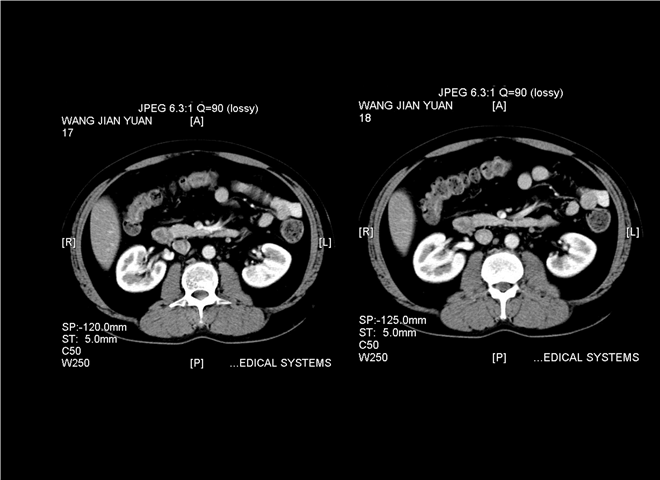

13_CT增强扫描